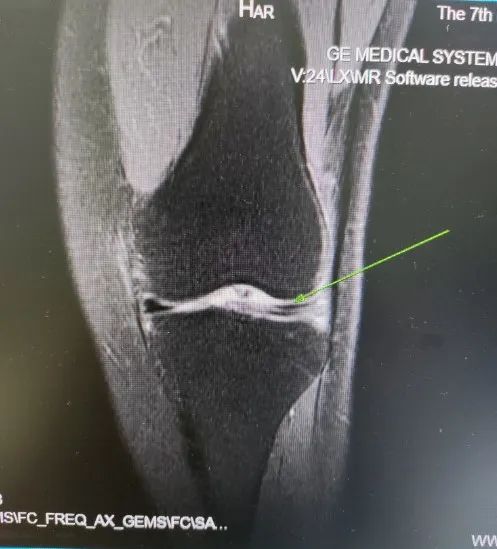

骨和关节病变

对于骨和关节病变,比如半月板的损伤、半月板的撕裂以及各个关节韧带的损伤,CT检查是无法替代的,建议用磁共振检查。